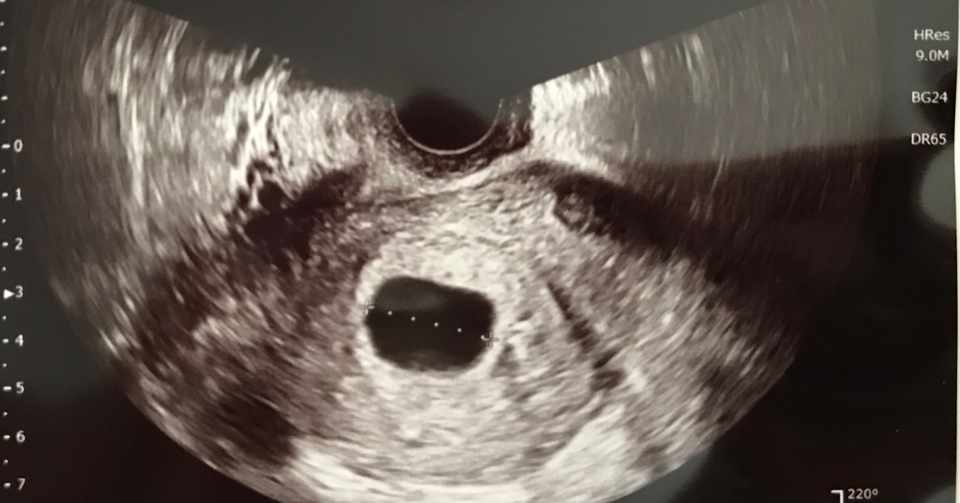

8 稽留流産の診断 日本産婦人科医会